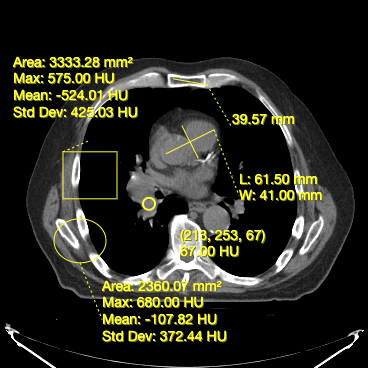

Cornerstone3DTools provide a set of annotation tools. You can use these tools to create and edit annotations for use cases such as:

• Measuring distance between two points (Length Tool)

• Measuring width and length for a structure (Bidirectional Tool)

• Measuring area and statistics for a rectangular area (RectangleRoi Tool)

• Measuring volume and statistics for a ellipsoid (EllipseRoi Tool)

Below, you can see a screenshot of the annotation tools that are available in Cornerstone3DTools.